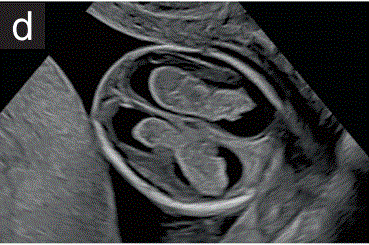

(2.4)在多胎妊娠中,应确定并记录绒毛膜和羊膜性(图2c)。

胎儿mt是什么检查什么疼吗【文献学习/规范指南】ISUOG实践指南(2023更新): 11-14周胎儿超声检查(全文)_https://www.jmylbn.com_新闻资讯_第8张

图2 11+0至14+0周时,可作为详细胎儿超声检查的一部分获得的解剖图。

(c)在多胎妊娠中,应通过寻求λ征(如双胎妊娠所示)或T来评估绒毛膜和羊膜。